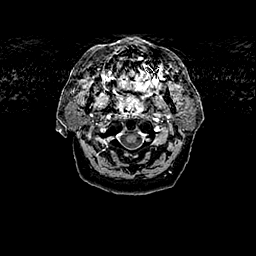

Glioma overlay -- Slice #0

[Home][Help][Clinical] Slice 0